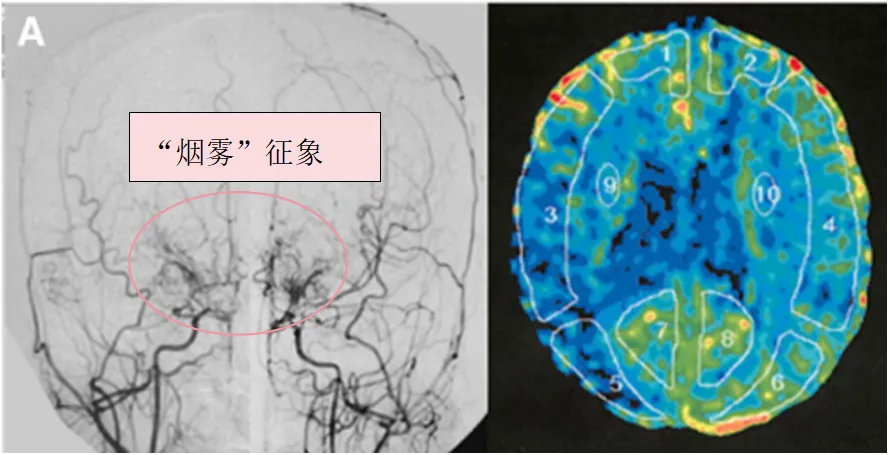

术前血管造影(双侧颈总动脉正位图)显示双侧颈内动脉末端存在"烟雾血管狭窄征象",双侧大脑中动脉(MCA)狭窄(左侧明显)。术前Xe-CT检查显示双侧MCA区域脑血流减少(右侧15.9,左侧22.8ml/100g/min)。